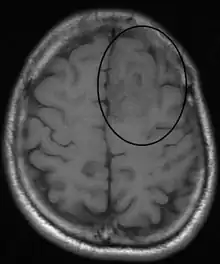

An oligodendroglioma as seen on MRI

Oligodendrogliomas are generally felt to be incurable using current treatments. However compared to the more common astrocytomas, they are slowly growing with prolonged survival. In one series, median survival times for oligodendrogliomas were 11.6 years for grade II.[18]